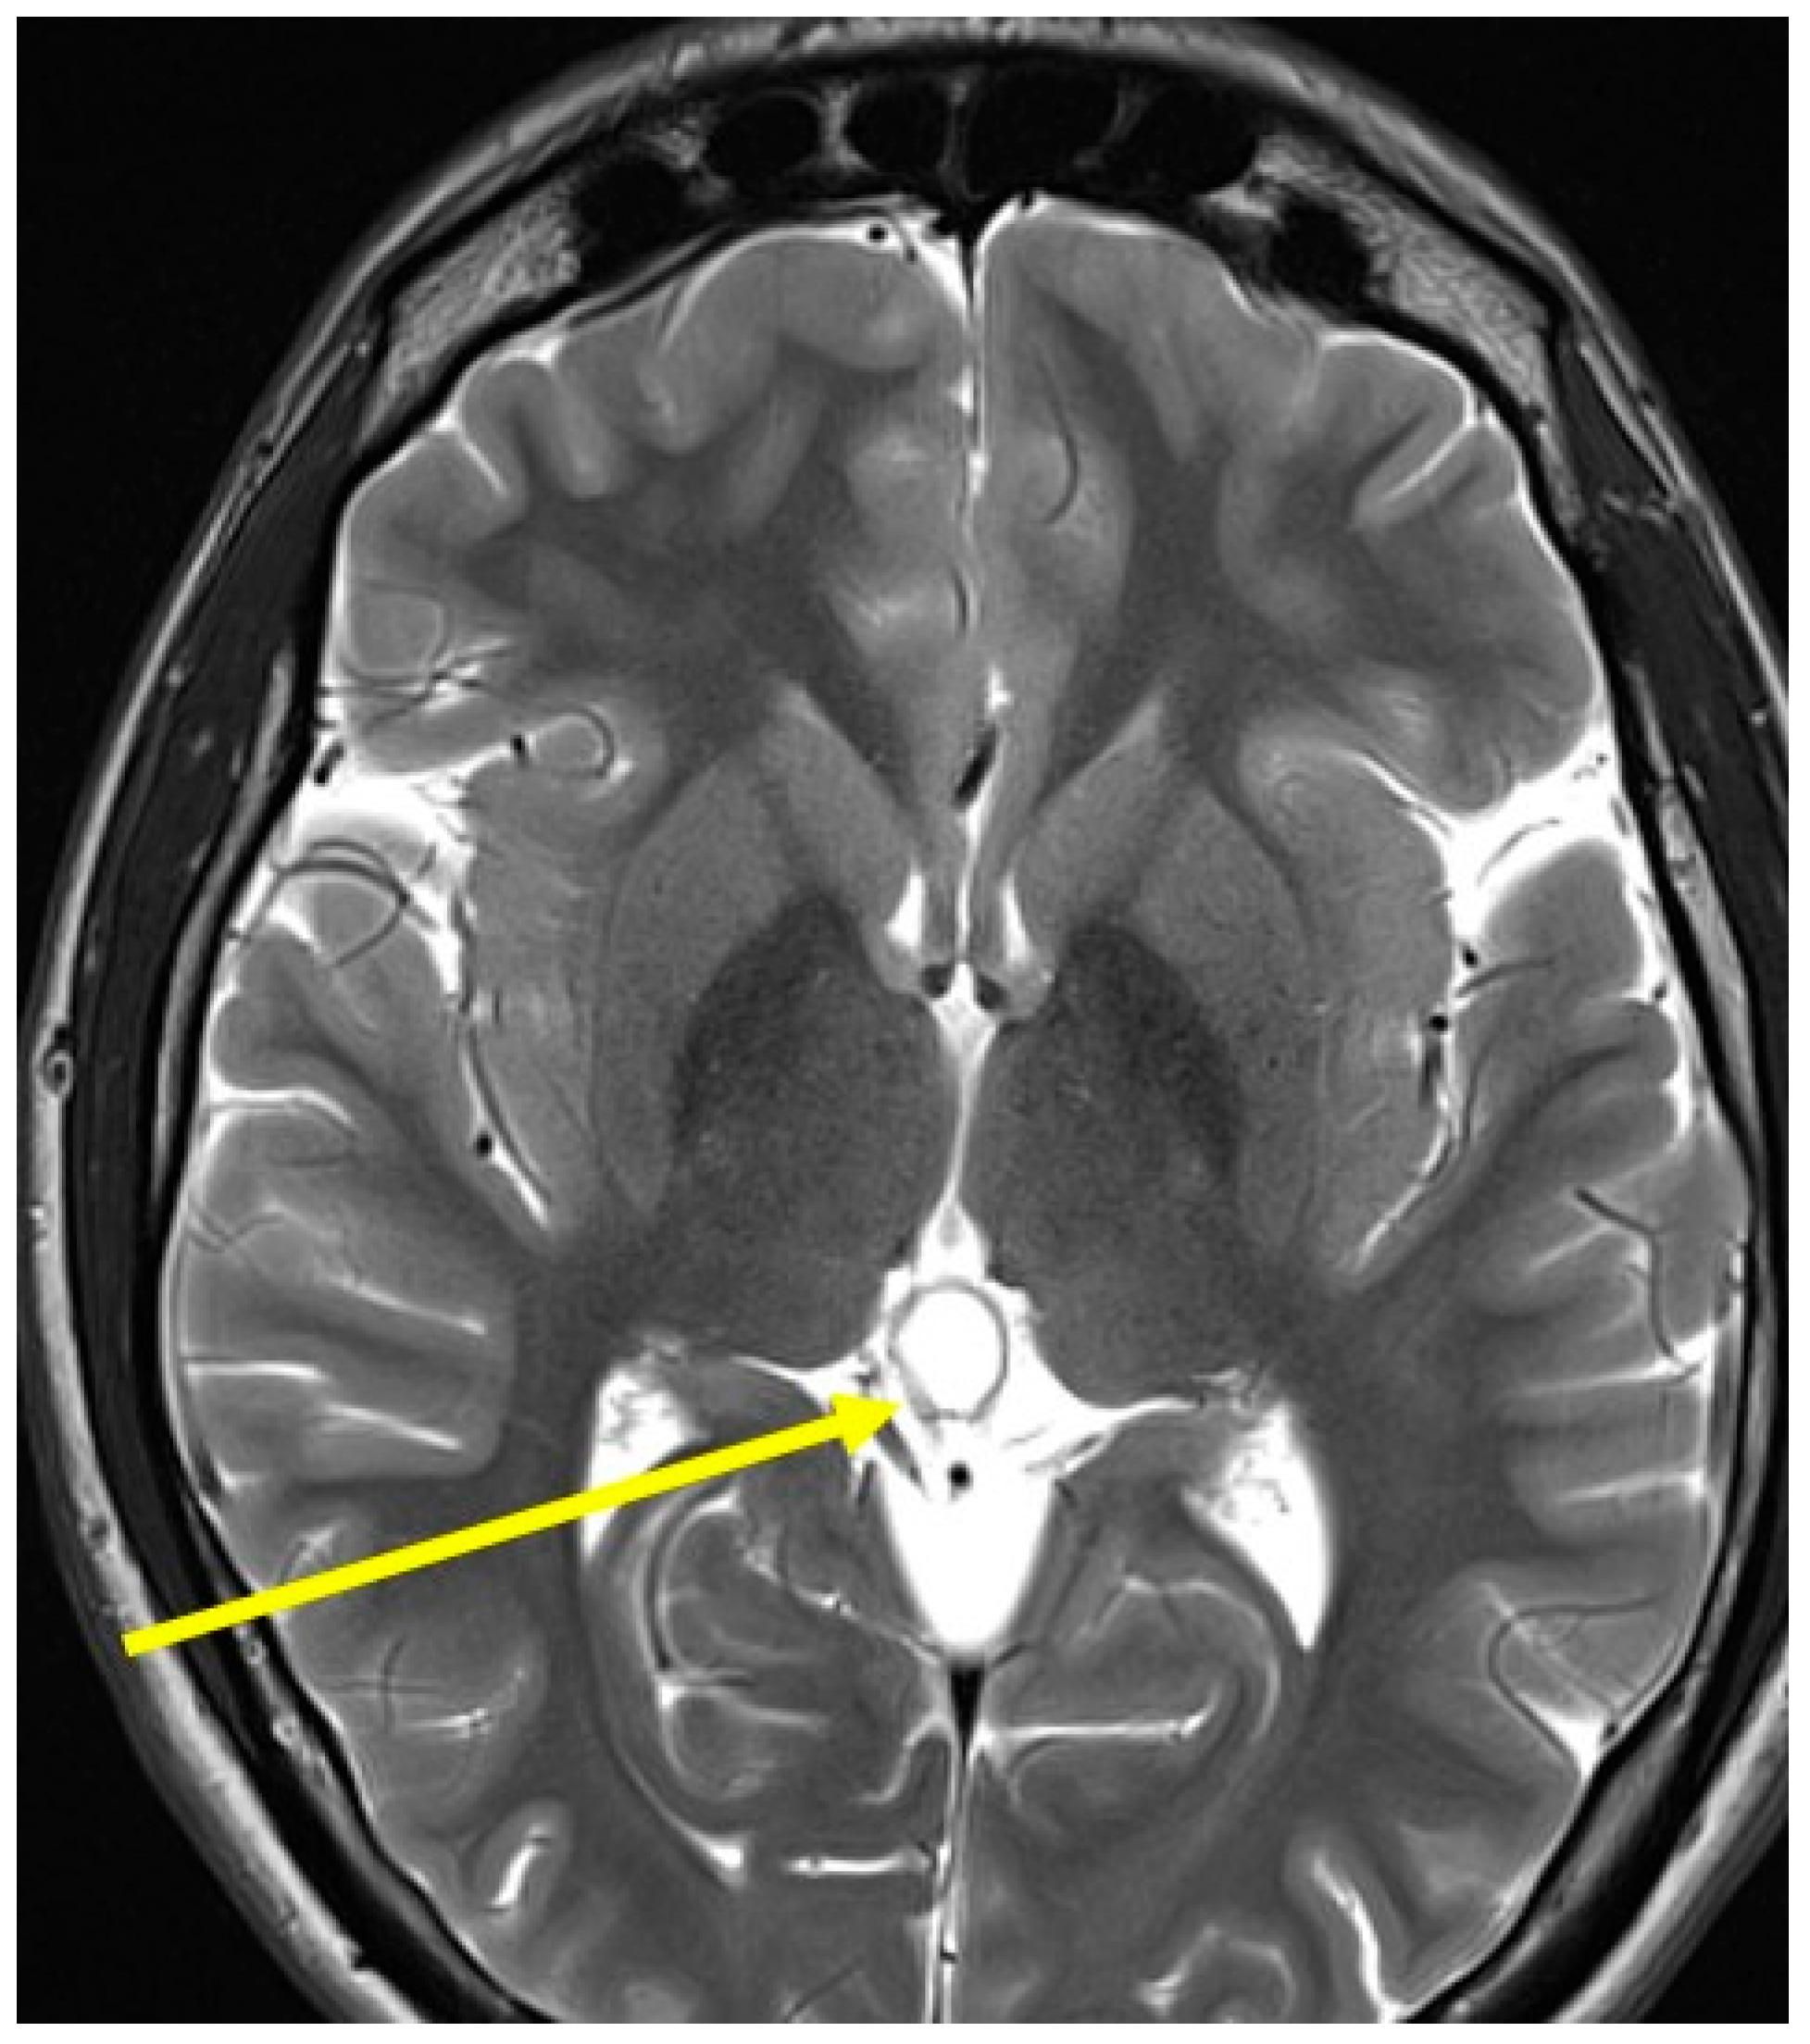

2. Case Presentations

3.3. Myasthenic Syndrome After SARS-CoV-2 Infection and Vaccination